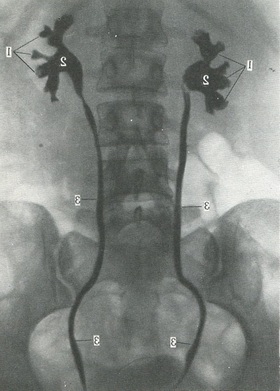

Висхідна пієлографія. При цьому способі дослідження через сечовідний катетер в ниркову балію вводиться газ або рідке контрастну речовину (рис. 322). При пієлографії виявляється дуже інтенсивна тінь малих і великих чашечок, миски і сечоводу. Якщо контрастна речовина вводиться під тиском, то можливі розриви малих чашечок і проникнення його в кровоносні і лімфатичні судини, мозковий і кіркова речовина нирки. У цьому випадку можливе скупчення контрастної речовини під фіброзною капсулою нирки. Цей процес називається мисково-ниркового рефлюксом.

322. Пієлографія з двостороннім контрастуванням.

1 - ниркові чашечки: 2 - балії нирок; 3 - сечоводи.